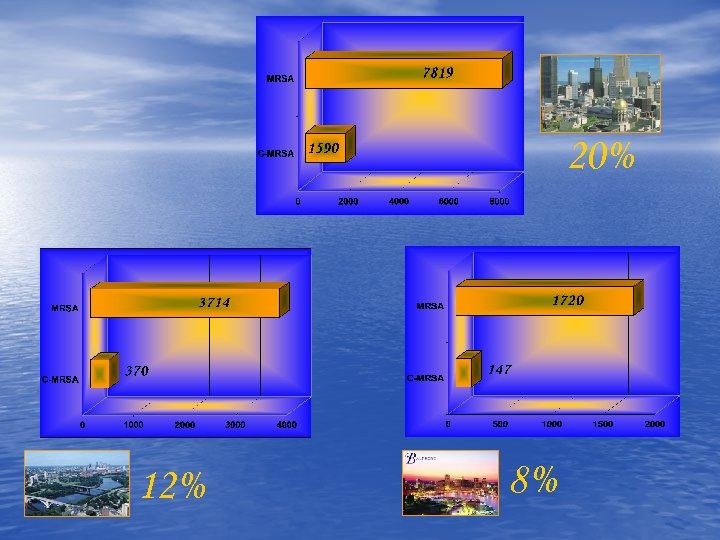

20% 12% 8%

20% 12% 8%